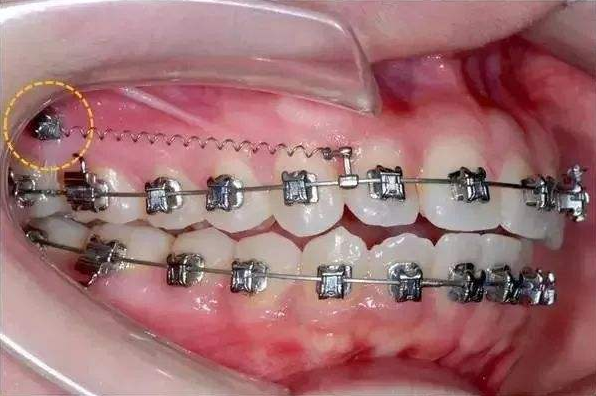

骨釘,顧名思義,是一種外形十分像釘子的種植釘,是放置在牙骨上方一個(gè)迷你的"釘子"。

它體積的小,好植入,近年來(lái),逐漸成為正畸科常用的正畸輔助工具。

可不要看它體積小,卻在多種正畸方案中,成為醫(yī)生的得力助手,扮演著至關(guān)重要的角色

但是有了骨釘植入,就可以解決前者調(diào)節(jié)方案的煩惱,可以根據(jù)不同的調(diào)節(jié)方案,不同的調(diào)節(jié)需求,在口腔中相應(yīng)的位置植入骨釘形成口腔中的一個(gè)受力點(diǎn),同時(shí)利用正畸器,橡皮筋相互拉力的作用下,更好的幫助醫(yī)生更好的控制牙齒的移動(dòng),做到"該移動(dòng)的牙移動(dòng),不該動(dòng)的牙不動(dòng)"從達(dá)到佳的調(diào)節(jié)果。